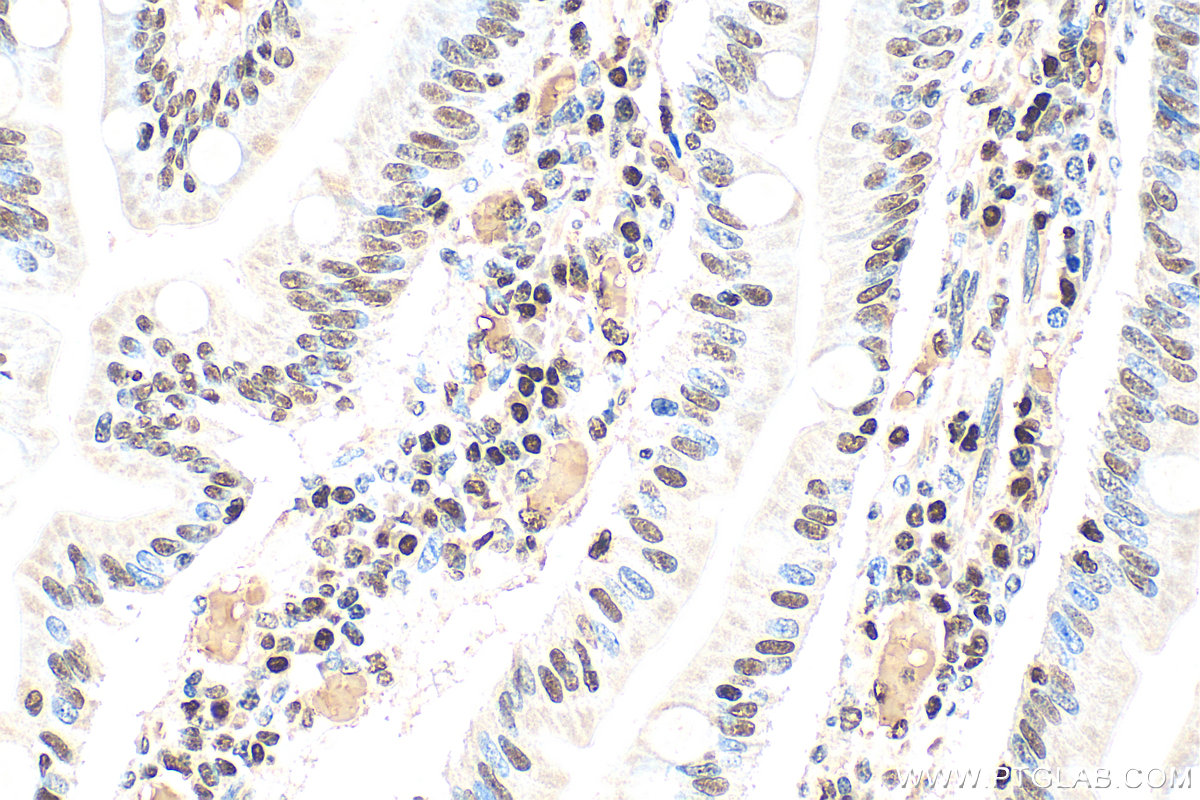

| Positive IHC detected in | human small intestine tissue Note: suggested antigen retrieval with TE buffer pH 9.0; (*) Alternatively, antigen retrieval may be performed with citrate buffer pH 6.0 |

| Immunohistochemistry (IHC) | IHC : 1:300-1:1200 |